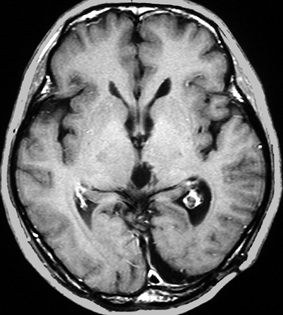

成人女性の松果体細胞腫で充実性腫瘍です。多少凹凸がありますがだいたい楕円形。中脳水道が閉塞して軽度の水頭症(頭の中に髄液が溜まる)になってきています。急性水頭症で急変して意識障害になることがありますので,迷わず摘出するか,第3脳室開窓術 ETVをしてから経過観察します。